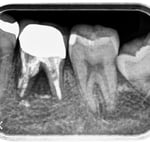

他院で抜歯と診断された症例です。友人の歯科医師の紹介で遠方から通院されました。初診時(左図)には、楔印で示すように、歯の根の先に黒い影が明瞭に写っています。が治療開始から8ケ月後(右図)では、黒い影は消えたり縮小しています。

歯の根の先の黒い影も消え(左図)、(手前は完全に消えていないが、完全な縮小傾向と症状がない)たので、クラウンを装着するための型採りをします。

右図の楔印は破折線です。破折線は特殊な方法で修復しています。